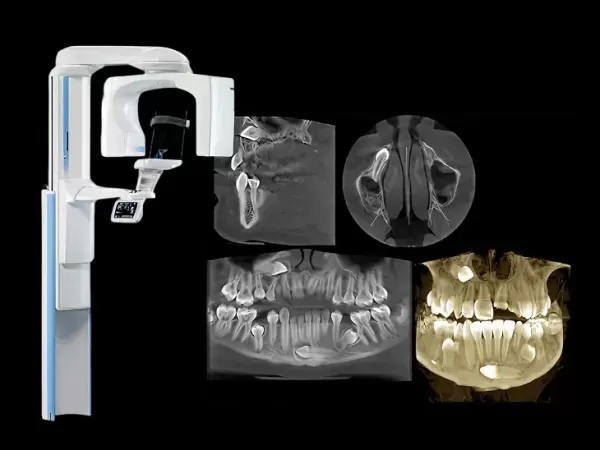

CBCT 3D - Иновативния Planmeca Viso™ G5, който има голям избор на различни обеми за изследване (FOV) - от Ø30 x 30 (ендодонтски) до Ø200 x 170 обем (за цялата лицева област).

- Voxel size: 75 μm*, 150 μm, 300 μm, 450 μm;

- възможността за промяна на вокселите, което ни дава възможност за промяна яркостта и контраста. Само Planmeca Viso™ G5 има интелигентен алгоритъм за корекция на движение Planmeca CALM™, той елиминира необходимостта от повторения, като отменя ефектите от движението на пациента. Където грешки не се допускат!

- Planmeca Viso™ G5 предлага уникалния протокол за изображения Planmeca Ultra Low Dose™, което позволява на денталните лекари да получават 3D изображения при значително по-ниски ефективни дози за пациента, без статистическо намаляване на качеството на изображението;

- Planmeca Viso™ G5 е единственият по рода си най-нов скенер в България, който има значително по-малко облъчване от на другите лаборатории.

Ортопантомограф - VistaPano S Ceph от Dürr Dental е нов модерен и щадящ пациентите немски томограф, който поставя нов стандарт за рязкост на екстраоралните изображения. 2D панорамният рентгенов апарат също е привлекателен поради лекотата си на работа и добре обмислен работен процес, който се поддържа от иновативен 7” сензорен дисплей.

- Много бързо сканиране за 4,1 секунди;

- Отлично качество и рязкост на изображението;

- Ниска доза радиация;

- Без промяна на сензора, вградени са 2 сензора от висок клас;

- Подходящ за млади пациенти - заради комбинацията от ниска рентгенова доза и кратко време за сканиране.